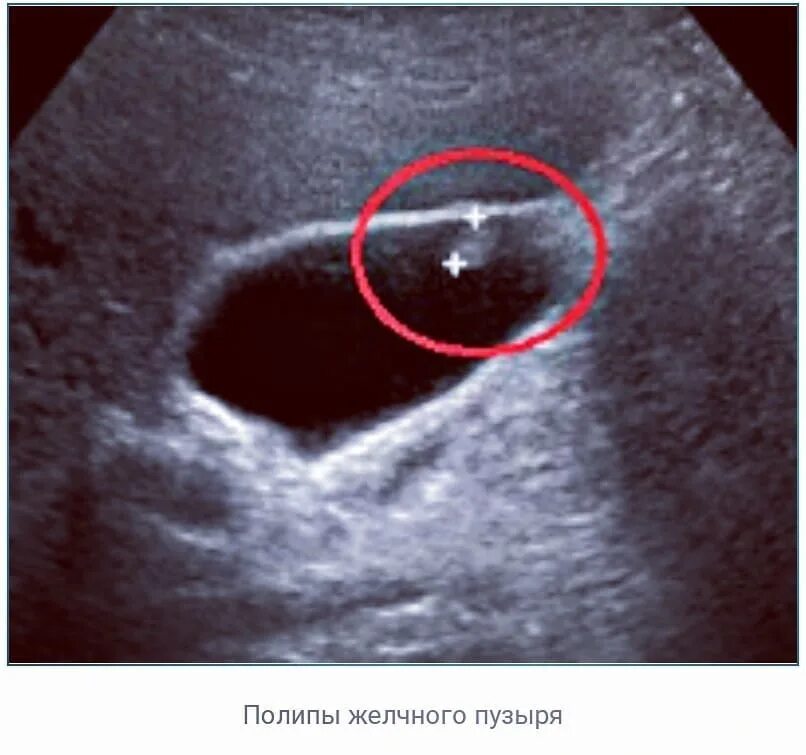

Какие полипы желчного пузыря